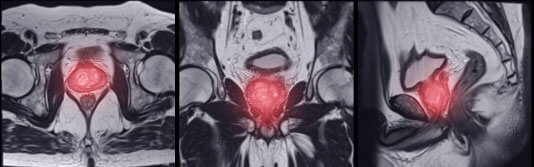

Restablece la salud de la glándula prostática

Vejiga Próstata

La prostatitis puede ser bacteriana o no bacteriana. En el primer caso, la enfermedad está causada por agentes patógenos (estafilococos, estreptococos), y en el segundo, por congestión pélvica.